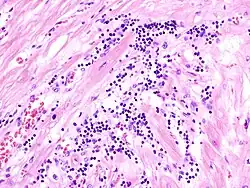

Virale Myokarditis

Ät.: Coxsackie-, ECHO-, Adenoviren, Influenzaviren

Pathogenese: Herzmuskelnekrose durch Virus und T-Zell-vermittelte Immunreaktion.

Mikro: Interstitielles lymphozytäres Infiltrat (kleine blaue Zellen), kaum Nekrosen.